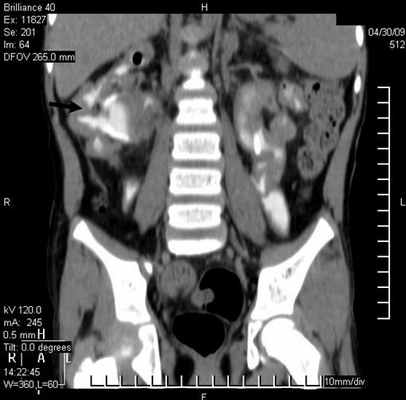

Результаты исследования и их обсуждение. Показаниями к выполнению МСКТ были расширение мочеточника. В 29 (78,4%) наблюдениях выявлен уретерогидронефроз различной степени, в 5 (13,5%) – эктопия устья мочеточников и в 3 (8,1%) - уретероцеле (рис. 1).

Дополнительные диагностические возможности открываются при реконструкции полученного изображения с применением тонких реконструируемых срезов (1,25 мм), а также построения мультипланарных реконструкций. При этом изменение со стороны мочеточника характеризовалось расширением (62,2%) и деформированием (29,7%) органа (рис 2.).